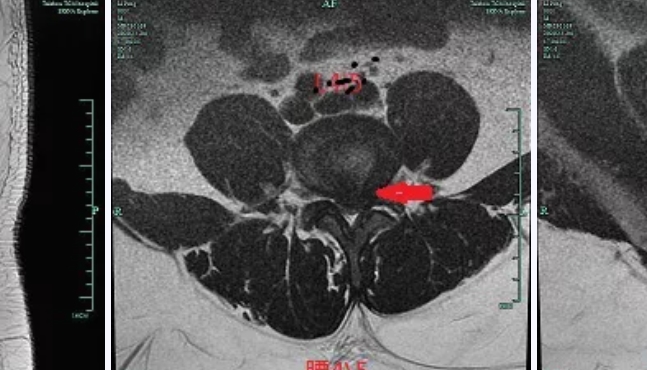

椎間孔鏡技術(shù)治療腰椎間盤突出癥,自2018年在我院開展以來,已經(jīng)成功治愈了不少病患。但近期的一個病例卻仍然讓我們印象深刻,更加感慨“椎間孔鏡技術(shù)”的魅力無限,小小內(nèi)鏡,卻能解決大大的煩惱。手術(shù)前手術(shù)后患者李某,31歲男性,家住路橋區(qū),挖掘機(jī)駕駛員,已經(jīng)被“腰椎間盤突出癥”折磨了6年,腰腿痛得已經(jīng)無法正常行走,跛行明顯。而這個病例的特別之處,并不是患者病程長,而是患者身高172cm,體重卻有252斤。患者自訴自己之前一直口服中藥、針灸推拿等,病情也是時輕時重。住院前2天因為勞累后導(dǎo)致腰痛伴左下肢放射性麻痛明顯,根本無法行走,在家臥床休息時剛好電視上在播放《阿福講健康》,欄目中顏峰副主任中醫(yī)師在講述“椎間孔鏡技術(shù)治療腰椎間盤突出癥”,患者被案例中的神奇療效所吸引。遂于2020年11月4日到顏峰副主任中醫(yī)師門診就診,經(jīng)仔細(xì)詢問病史查體后,考慮“腰椎間盤突出癥”,為了進(jìn)一步了解病情,建議患者行腰椎MRI、CT檢查,檢查結(jié)果(見下圖)提示腰4/5、腰5/骶1椎間盤突出明顯,神經(jīng)根明顯受壓,且由于突出時間長,突出的髓核嚴(yán)重鈣化。腰椎MR腰椎間盤CT經(jīng)過科室內(nèi)討論,一致認(rèn)為患者癥狀體征與影像學(xué)表現(xiàn)相符,符合手術(shù)指征??紤]到患者的體重、雙節(jié)段突出及髓核鈣化等因素,使得手術(shù)的難度、手術(shù)時間都大大增加,在與患者及家屬充分溝通后,擬行“椎間孔鏡下腰4/5、腰5/骶1椎間盤突出髓核摘除術(shù)”。入院完善術(shù)前檢查及術(shù)前準(zhǔn)備后,于2020年11月6日在局麻下由顏峰副主任中醫(yī)師主刀行“椎間孔鏡下腰4/5、腰5/骶1椎間盤突出髓核摘除術(shù)”,術(shù)中進(jìn)展順利,在對神經(jīng)根減壓松解充分后,患者腰腿痛即刻緩解。患者術(shù)后腰部僅僅只有2個7mm左右的切口,腰腿痛完全消失,行走自如,高興地感嘆道“如獲新生”。骨三科團(tuán)隊介紹臺州市中醫(yī)院骨傷科是浙江省“十三五”重點學(xué)科,骨三科定位為微創(chuàng)骨科,現(xiàn)有副主任醫(yī)師3名,主治醫(yī)師1名,住院醫(yī)師1名。在科主任顏峰醫(yī)師帶領(lǐng)下,團(tuán)隊主要應(yīng)用微創(chuàng)技術(shù)及微創(chuàng)理念治療創(chuàng)傷、脊柱、關(guān)節(jié)疾病,開展了復(fù)合損傷的肢體功能重建,椎間孔鏡下治療椎間盤突出及椎管狹窄,微創(chuàng)脊柱內(nèi)固定,肩肘髖膝關(guān)節(jié)置換等手術(shù)。同時,作為中醫(yī)院特色科室,在骨質(zhì)疏松,中醫(yī)正骨理療,脊柱和關(guān)節(jié)退行性變保守治療方面有良好口碑。預(yù)約咨詢電話:0576-88825715骨三科也可掃描二維碼添加醫(yī)生微信咨詢